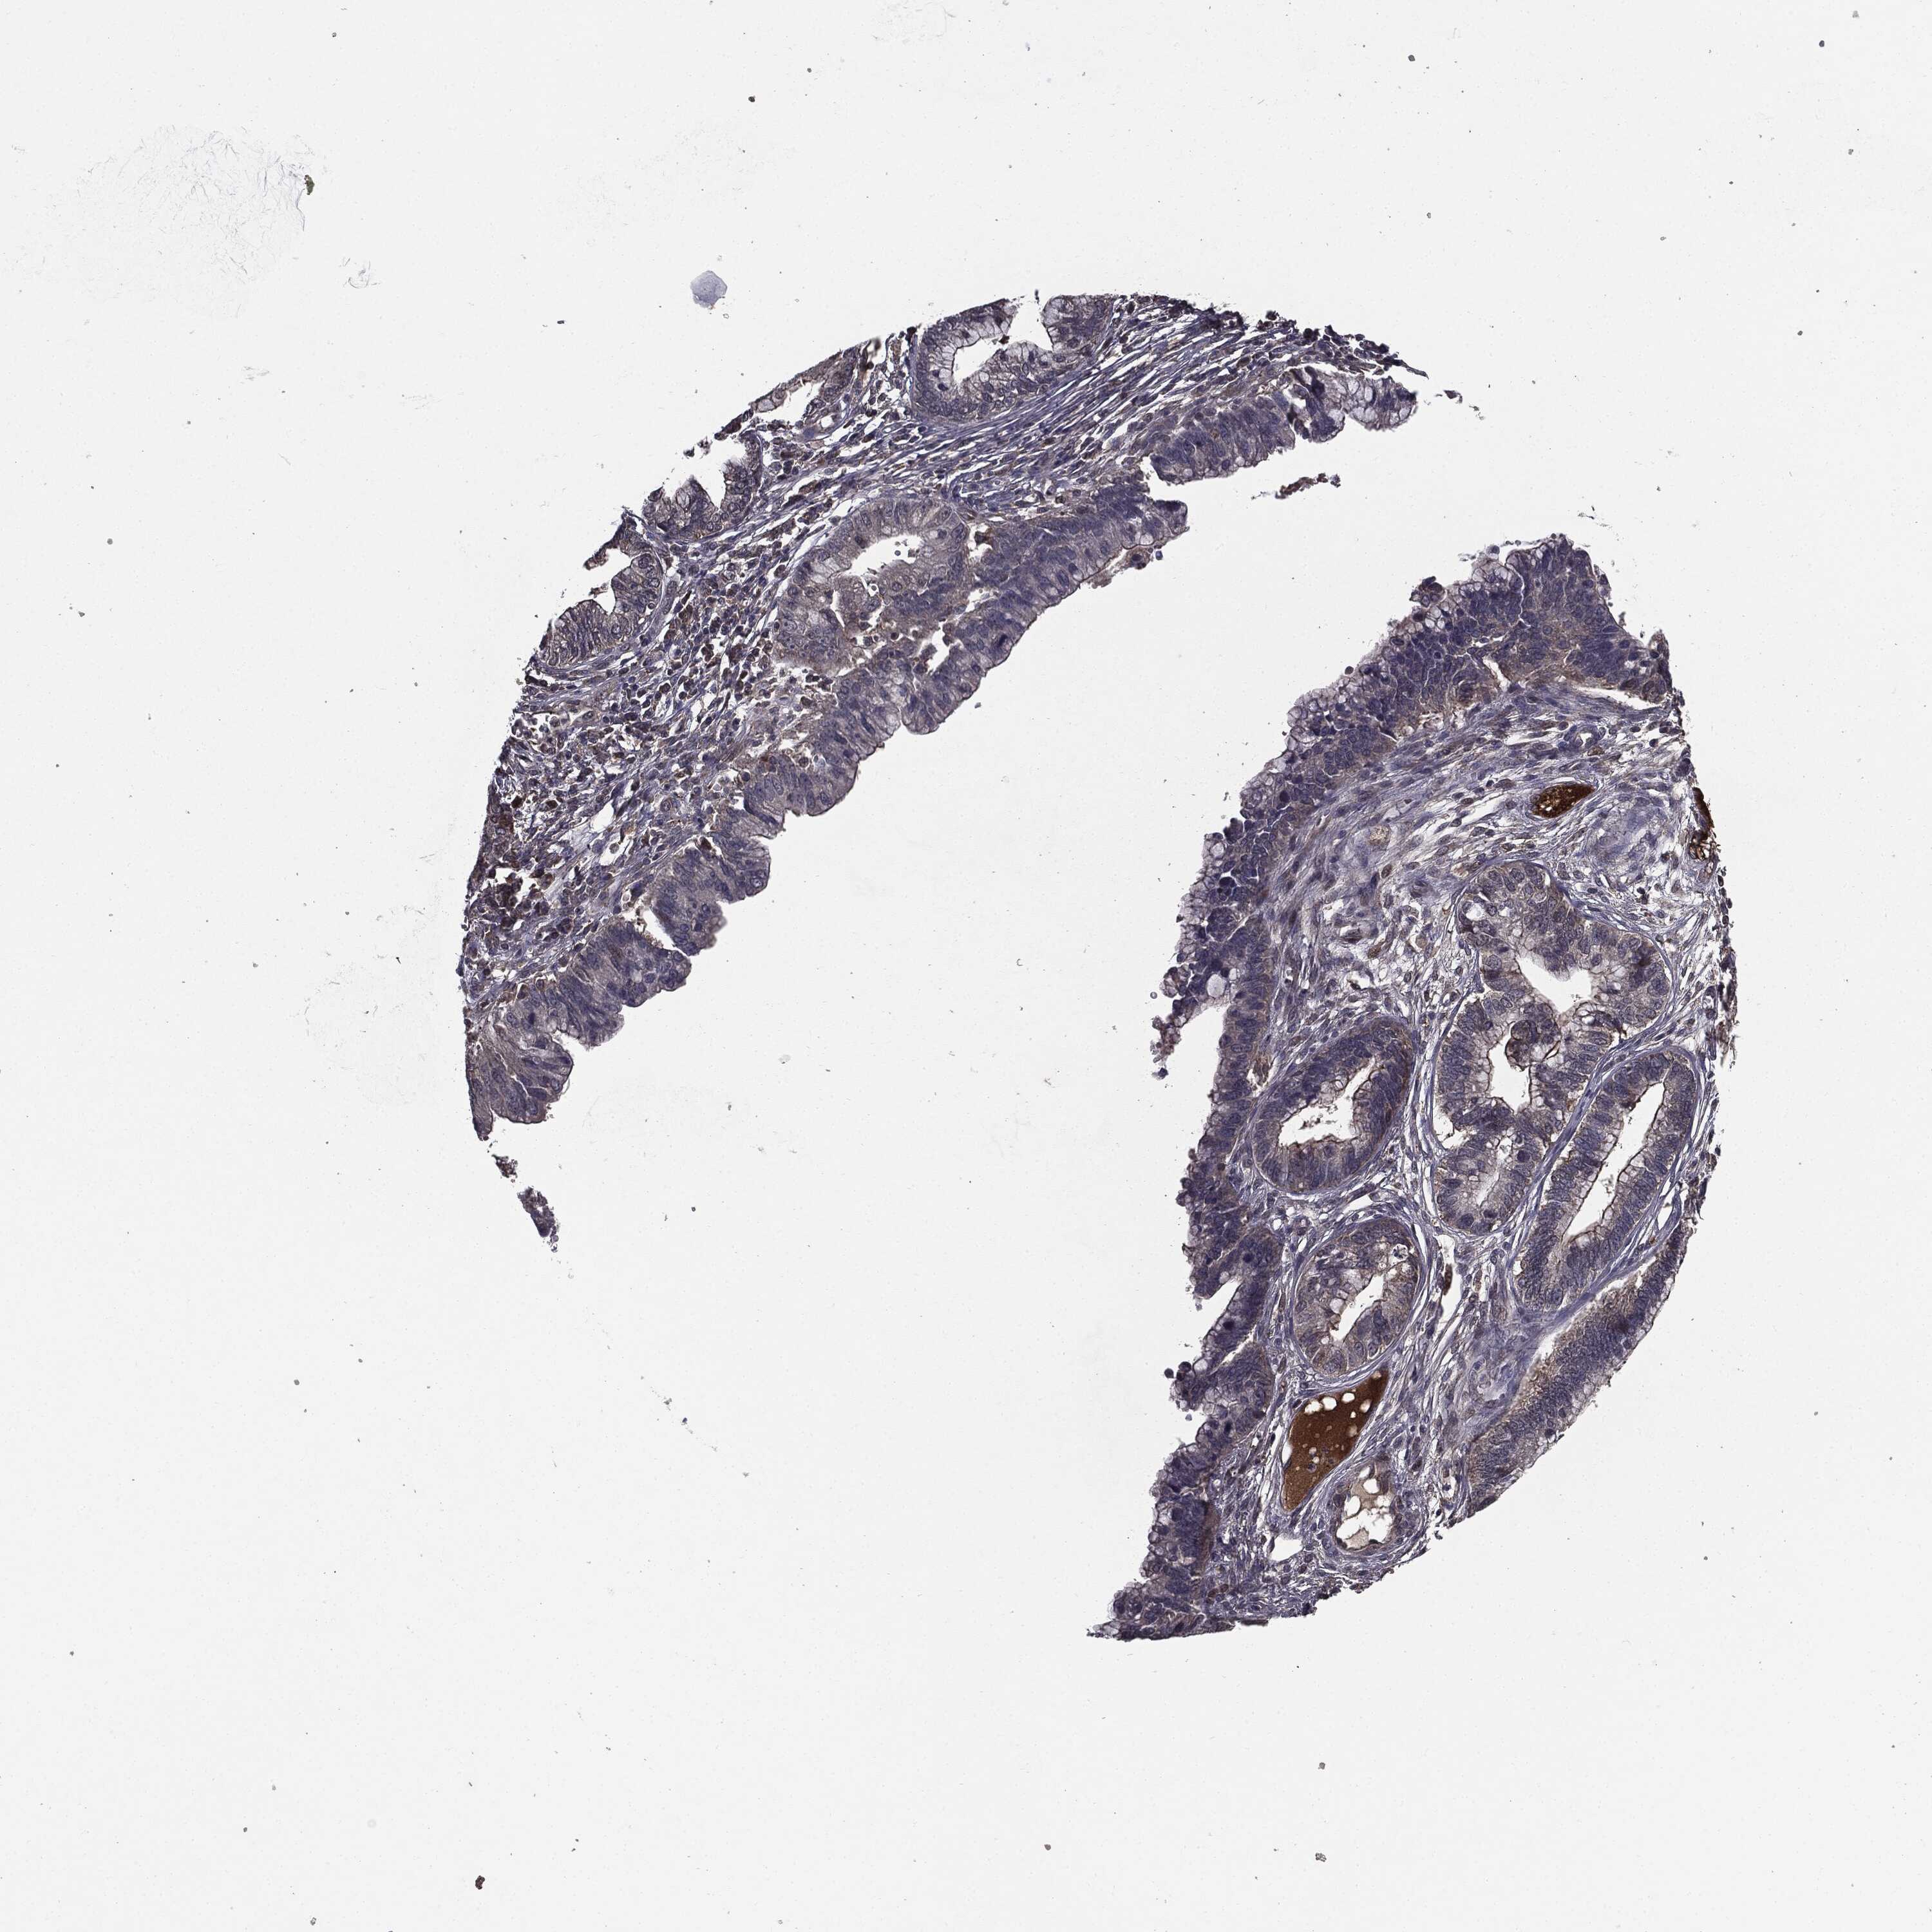

CERVICAL CANCER - Protein expressioni

A mouse-over function shows sample information and annotation data. Click on an image to view it in a full screen mode. Samples can be filtered based on level of antibody staining by selecting one or several of the following categories: high, medium, low and not detected. The assay and annotation is described here.

Note that samples used for immunohistochemistry by the Human Protein Atlas do not correspond to samples in the TCGA dataset.

Antibody stainingi

Antibody staining in the annotated cell types in the current human tissue is reported as not detected, low, medium, or high, based on conventional immunohistochemistry profiling in selected tissues. This score is based on the combination of the staining intensity and fraction of stained cells.

Each image is clickable and will lead to virtual microscopy that enables deeper exploration of all samples and also displays staining intensity scores, fraction scores and subcellular localization as well as patient and tissue information for each sample.

Antibody HPA052606

Antibody HPA077139

Staining

High

Medium

Low

Not detected

Intensity

Strong

Moderate

Weak

Negative

Quantity

>75%

75%-25%

<25%

None

Location

Nuclear

Cytoplasmic/membranous

Cytoplasmic/membranous,nuclear

Squamous cell carcinoma, NOS

Adenocarcinoma, NOS